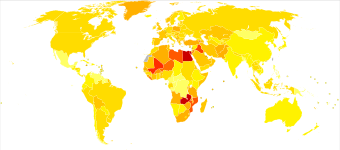

Epidemiology

Worldwide

Globally, in 2010, bladder cancer resulted in 170,000 deaths up from 114,000 in 1990.[48] This is an increase of 19.4%, adjusted for increase in total world population.

US

In the United States, bladder cancer is the fourth most common type of cancer in men and the ninth most common cancer in women. More than 50,000 men and 16,000 women are diagnosed with bladder cancer each year. Smoking can only partially explain this higher incidence in men.[49] One other reason is that the androgen receptor, which is much more active in men than in women, plays a major part in the development of the cancer.[50]

UK

Bladder cancer is the seventh most common cancer in the UK (around 10,400 people were diagnosed with the disease in 2011), and it is the seventh most common cause of cancer death (around 5,200 people died in 2012).[51]